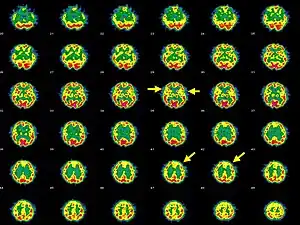

Brain SPECT transaxial images of a patient afflicted with Hashimoto's encephalopathy. | |